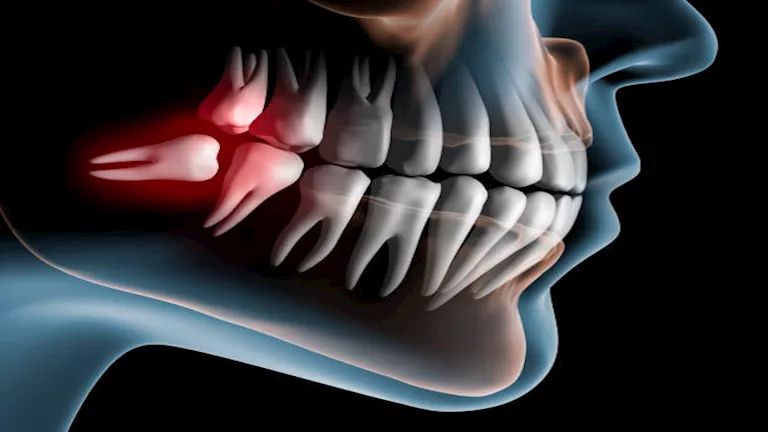

يُعد نزيف اللثة بعد خلع ضرس العقل من الأعراض الشائعة، خاصة خلال أول 24 ساعة، حيث يبدأ الجسم في تكوين جلطة دموية لحماية مكان الجرح وتسريع الالتئام.

1- زوال الجلطة الدموية (Dry Socket)

تُعد حالة Dry Socket من أبرز أسباب النزيف، وتحدث عندما لا تتكوّن الجلطة الدموية بشكل صحيح أو تتحرك من مكانها، ما يعرّض العظام والأعصاب ويؤدي إلى ألم شديد ونزيف مستمر.